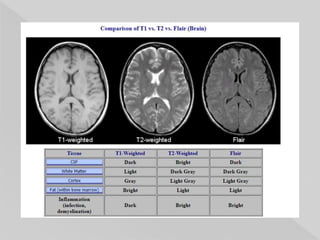

 repetition time (TR): long

 echo time (TE): long

 flip angle: less important than with T1

weighting

 Fat: intermediate-bright

 Fluid: bright

Fat – bright

White matter –

Dark

Gray matter -

White

CSF – Bright